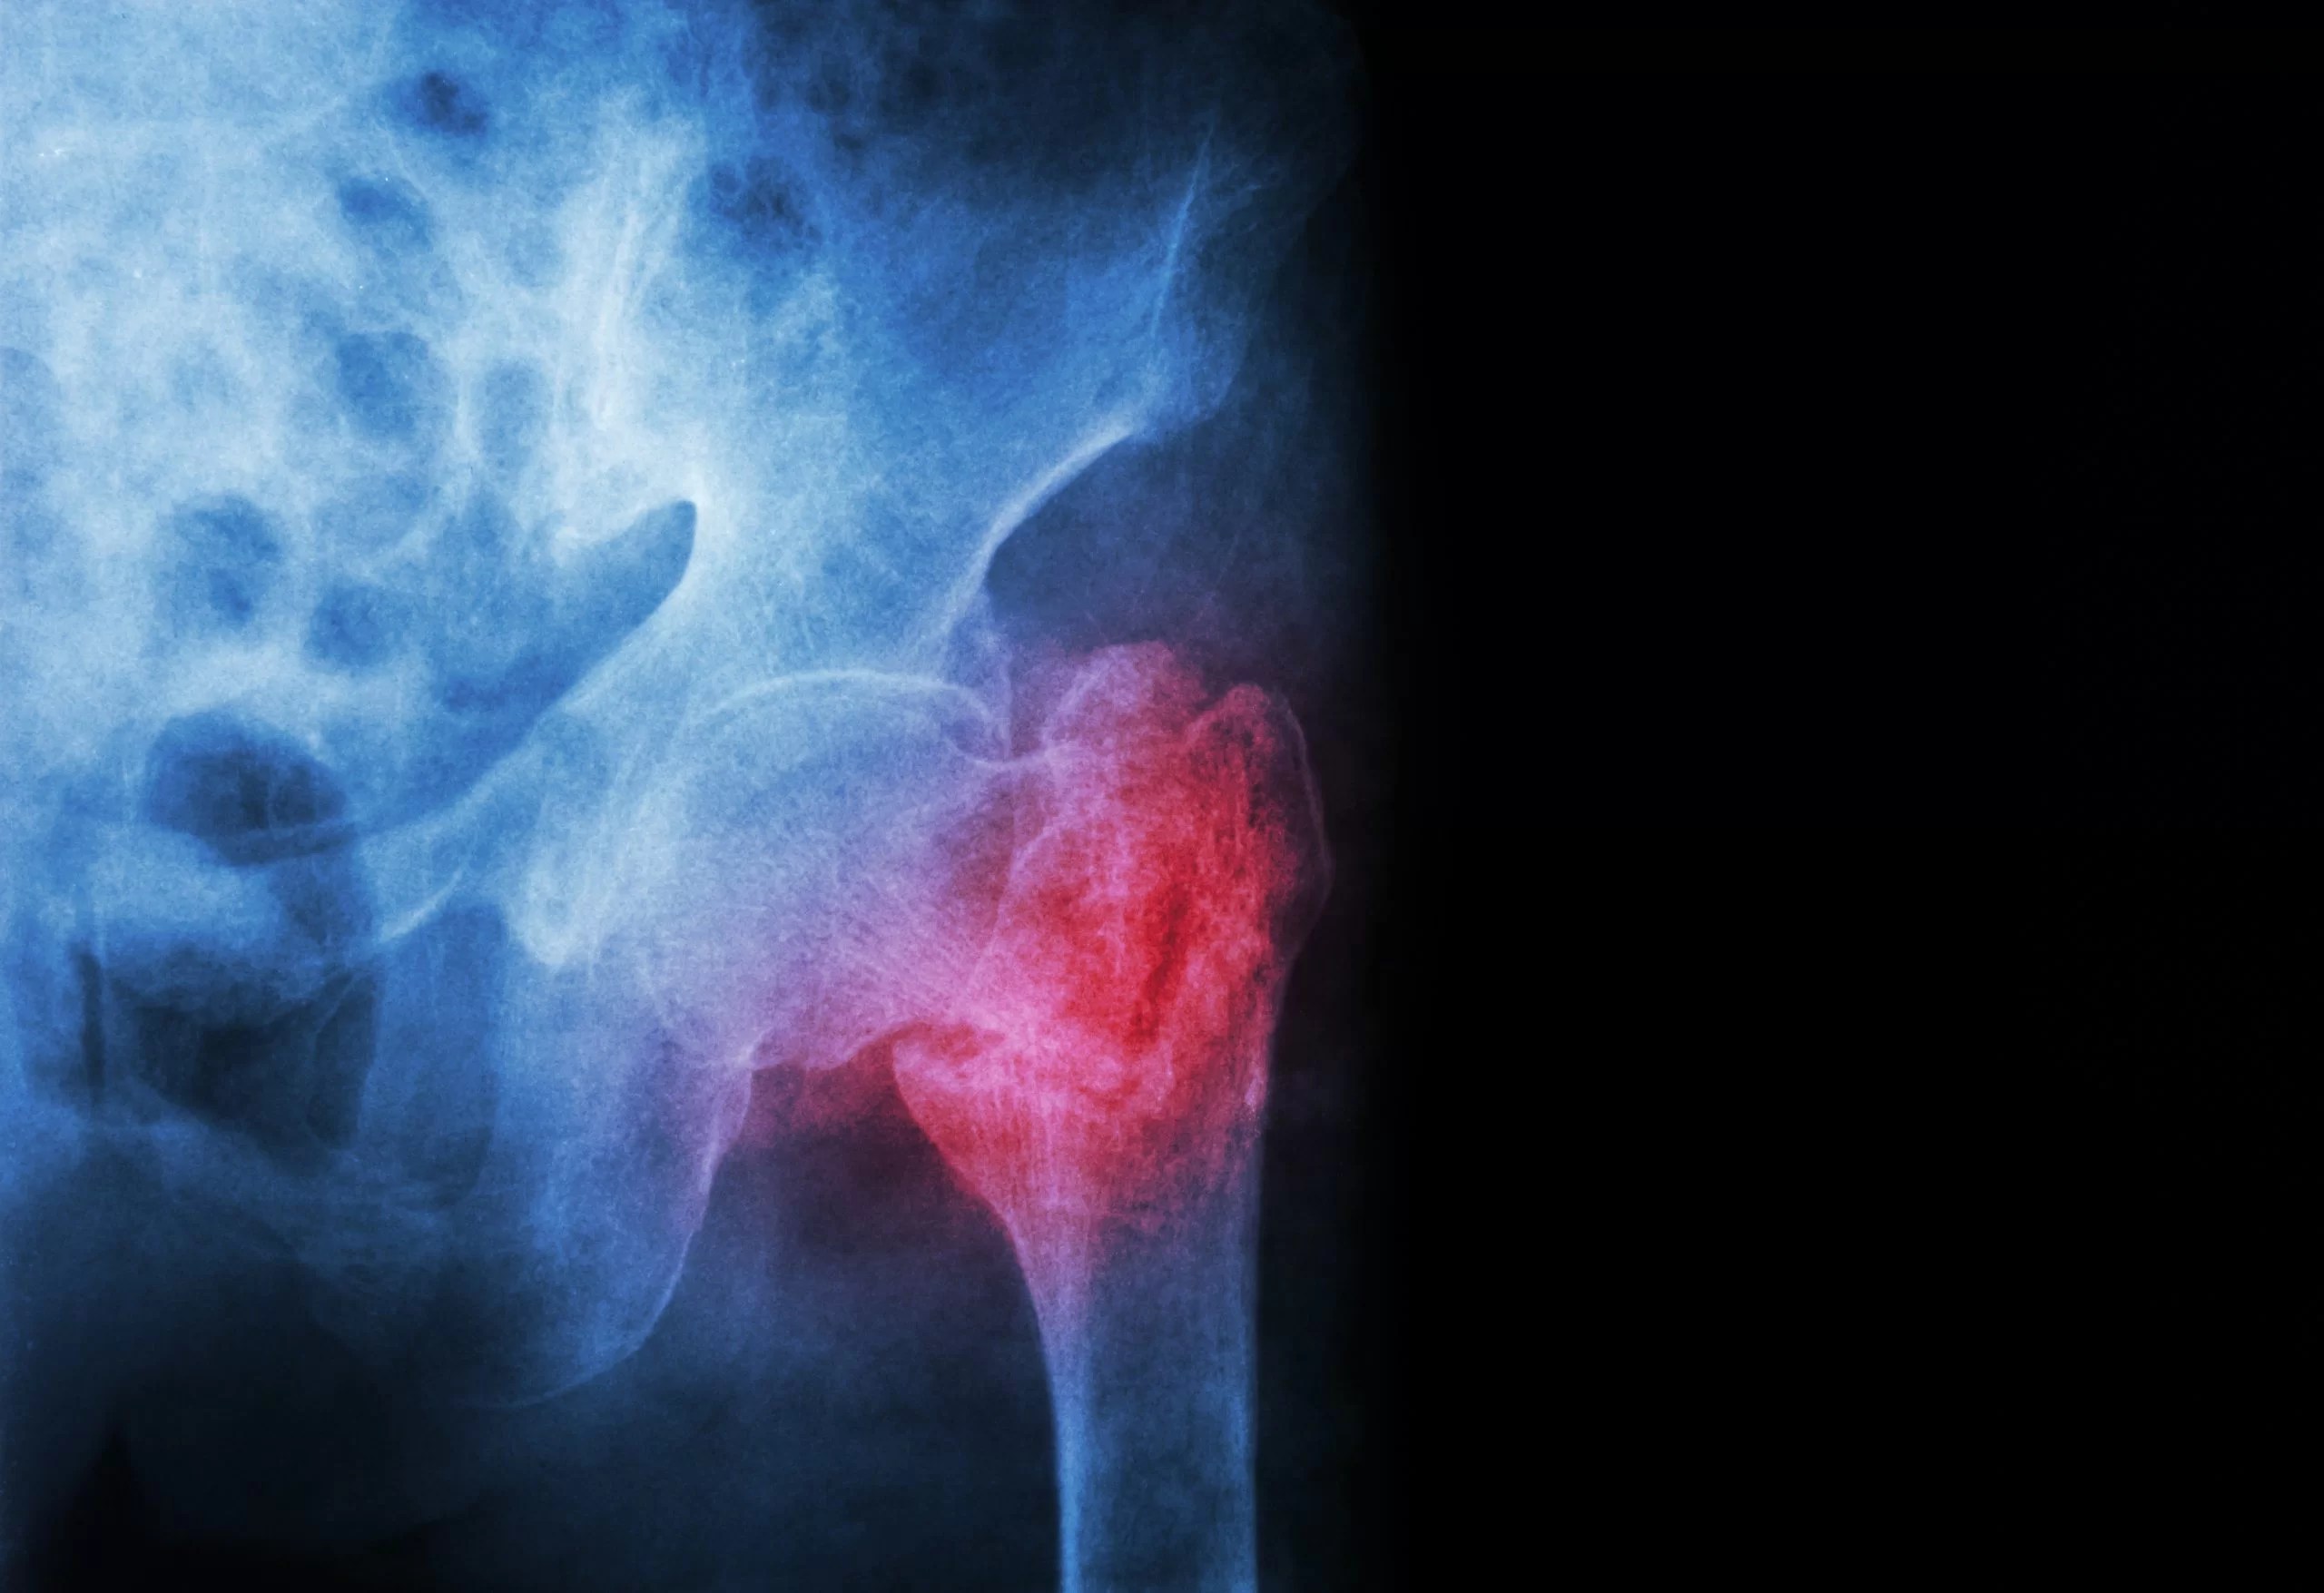

Bone union is revealed in the radiography (A) and computed tomography How Long Does Bone Union Take For bone healing to happen, the bone needs adequate stability and blood supply. One of the essential elements needed to undertake the proper course of treatment to restore functions lost as a result of fracture is. If it has been months since your surgery and your fracture is not healing or if you have continued pain after your surgery, you. How Long Does Bone Union Take.